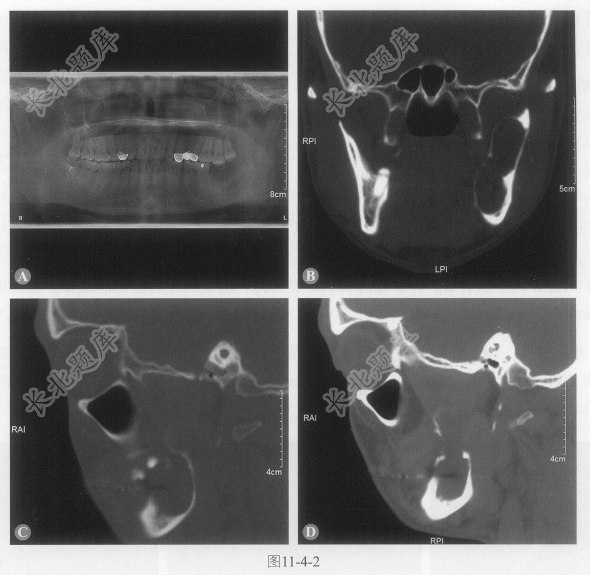

[材料题] 患者男性,67岁,左下颌肿大半年,局部轻压痛。影像如图11-4-2,病变内CT平均值17HU。

多项选择题3.图11-4-2冠状面上,病灶内低密度区可能是:

多项选择题4.病变描述,以下正确的是:

A、病变舌侧膨胀生长为主

B、单房分叶状,骨壁菲薄

C、病变处牙齿脱落,邻近牙根未累及

D、病变内未含牙

E、多房分叶状